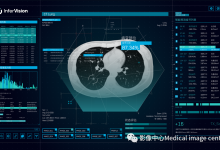

人工智能技术的快速发展正在引领医学影像诊断领域的革新。随着深度学习技术的不断成熟,其在医学影像诊断中的应用也日益广泛。本文将介绍人工智能技术在影像诊断中的应用及展望,并对相关产业发展现状和存在的问题进行分析。

随着人工智能(AI)技术的快速发展,AI在医学影像学中的应用也逐渐成熟。目前的研究大多数集中在对疾病进行影像评估的应用场景,对于医学影像科全流程化管理的研究并不多见。本文主要从全流程管理的概念、AI技术在其中的进展进行探讨及展望,以推进AI在医学影像科全流程管理应用场景的落地